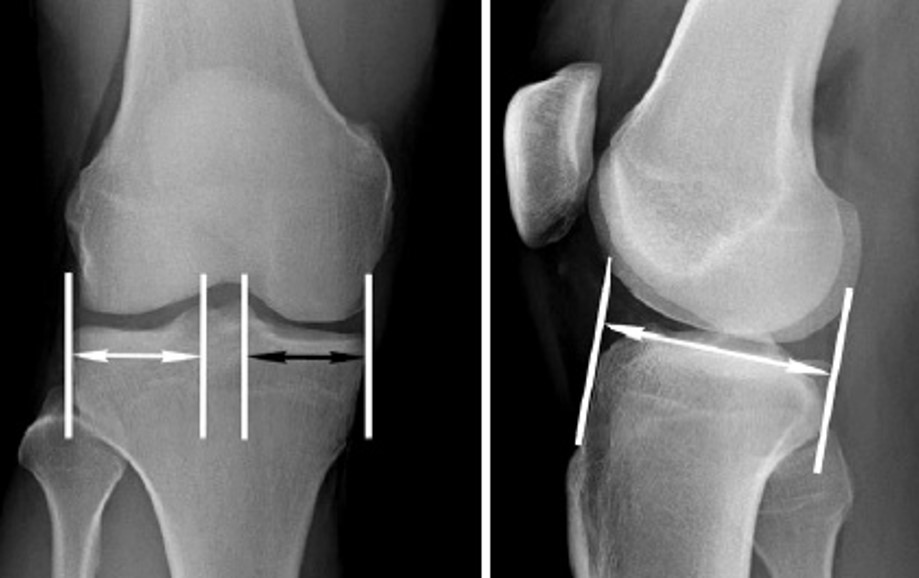

수술을 할때 meniscus의 width, length 측정이 중요합니다. width는 바로 측정을 해보면 되지만 (spine 기준) length의 경우 sagittal 길이의 70%를 LM, 80%를 MM 으로 생각하면 됩니다. hooked depth gauge 를 fine 하게 조정을 잘 하는 과정이 중요합니다.